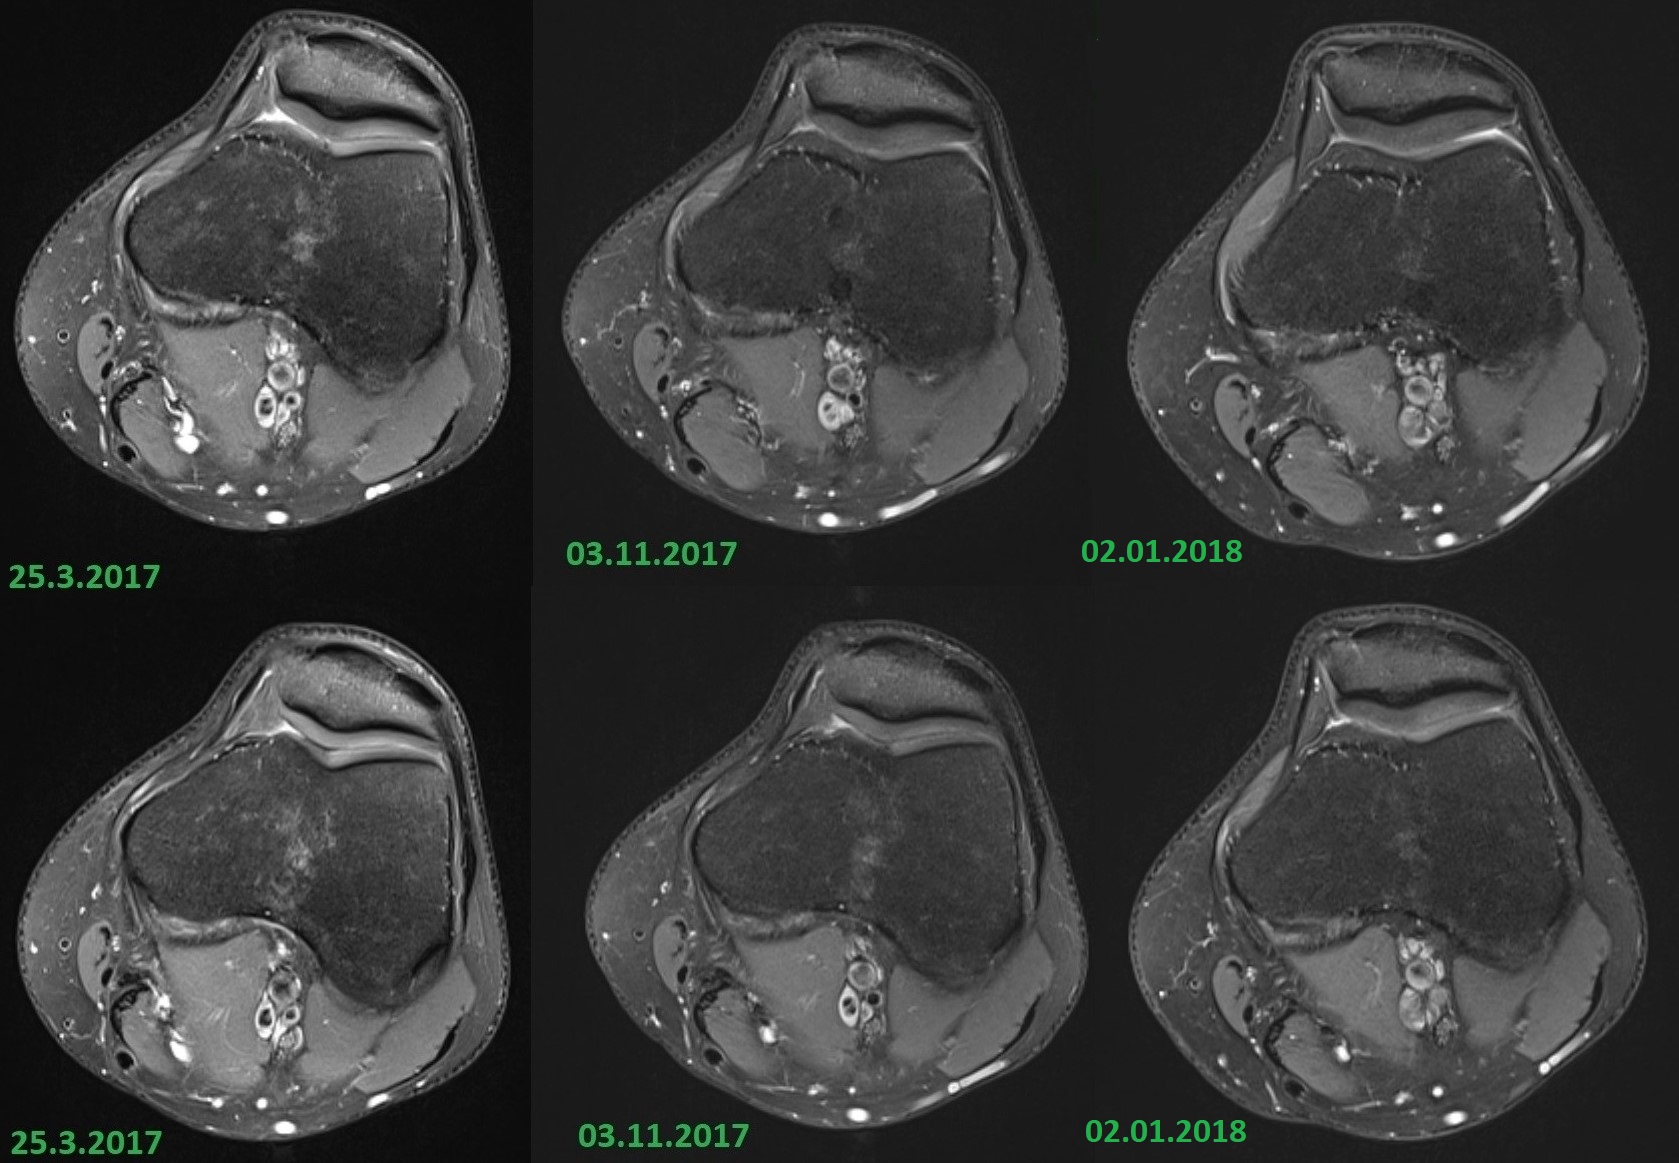

Ich ging nach Berlin erneut zu einem Orthopäden, der mir direkt eine Überweisung ins MRT gab. Er schaute sich die MRT Bilder vom März und die aktuelleren vom November an und erkannte auf beiden Bildern ein helles Ödem in der Kniescheibe. Dieses sollte nach 6 Wochen Laufpause bis Weihnachten verschwunden sein. Ich durfte währenddessen wieder locker radeln.

Der Radiologe hatte alle Bilder (März, November, Silvester) vorliegen, sie gedeutet und verglichen. Er sagte, dass die Beschwerden seiner Meinung nach nicht mit dem Ödem in der Kniescheibe zusammenhängen. Zudem ist der Haarriss im Schienbeinkopf trotz Pause zwischen November und Silvester wieder stärker zu sehen. Er kann sich das auch nicht erklären.

Meine Knie sehen im MRT (fast) gesund aus. Leichtes Ödem in der Kniescheibe, das laut Radiologe nicht Urheber der Beschwerden ist. Dieses Ödem ist in der Pause in keinster Weise abgeheilt. Und nun ist der Haarriss im Schienbeinkopf wieder prägnanter trotz Pause.

Ich hoffe man kann die vergleichenden Bilder erkennen. Man sieht das helle Ödem in der Kniescheibe (Querschnitte), die Haarrisse im Schienbeinkopf (Frontalsicht) und die Stressreaktion im vorderen Bereich (seitliche Sicht).

Der Radiologe kann sich nicht erklären wie ein Ödem in der Kniescheibe entstehen kann, solange man nicht darauf fällt. Normalerweise hält die Kniescheibe den Zugkräften im Knie stand. Er sieht das Ödem nicht als Urheber meiner Symptome, anders als der Orthopäde. Außerdem ist das Ödem in der Kniescheibe in den 6 Wochen Pause unverändert geblieben, obwohl der Orthopäde sagte, dass sowas in 6 Wochen ausheilt. Kann man den Knochenstoffwechsel irgendwie fördern? Ich hatte beispielsweise Calciumtabletten gekauft und über 5 Wochen genommen. Hat nicht geholfen. Ich bin gespannt, was der Orthopäde sagt, wenn er sieht, dass das Ödem nach wie vor da ist.

Die Kniescheibe find ich jetzt nicht sooo auffällig, die Oberfläche ist etwas aufgeraut,das gibt es aber auch physiologisch. Die helleren Bereiche in der Kniescheibe deuten mMn nicht auf ein Ödem, die Kniescheibe ist ja konvex geformt und weist daher auch unterschiedliche Stärken auf. (Aber das ist nur meine persönliche Meinung !!!! Ich lehn mich damit ziemlich weit aus dem Fenster !!!)

Die Auffälligkeiten am Schienbeinkopf finde ich schon eher auffällig bezüglich Knochenödem....